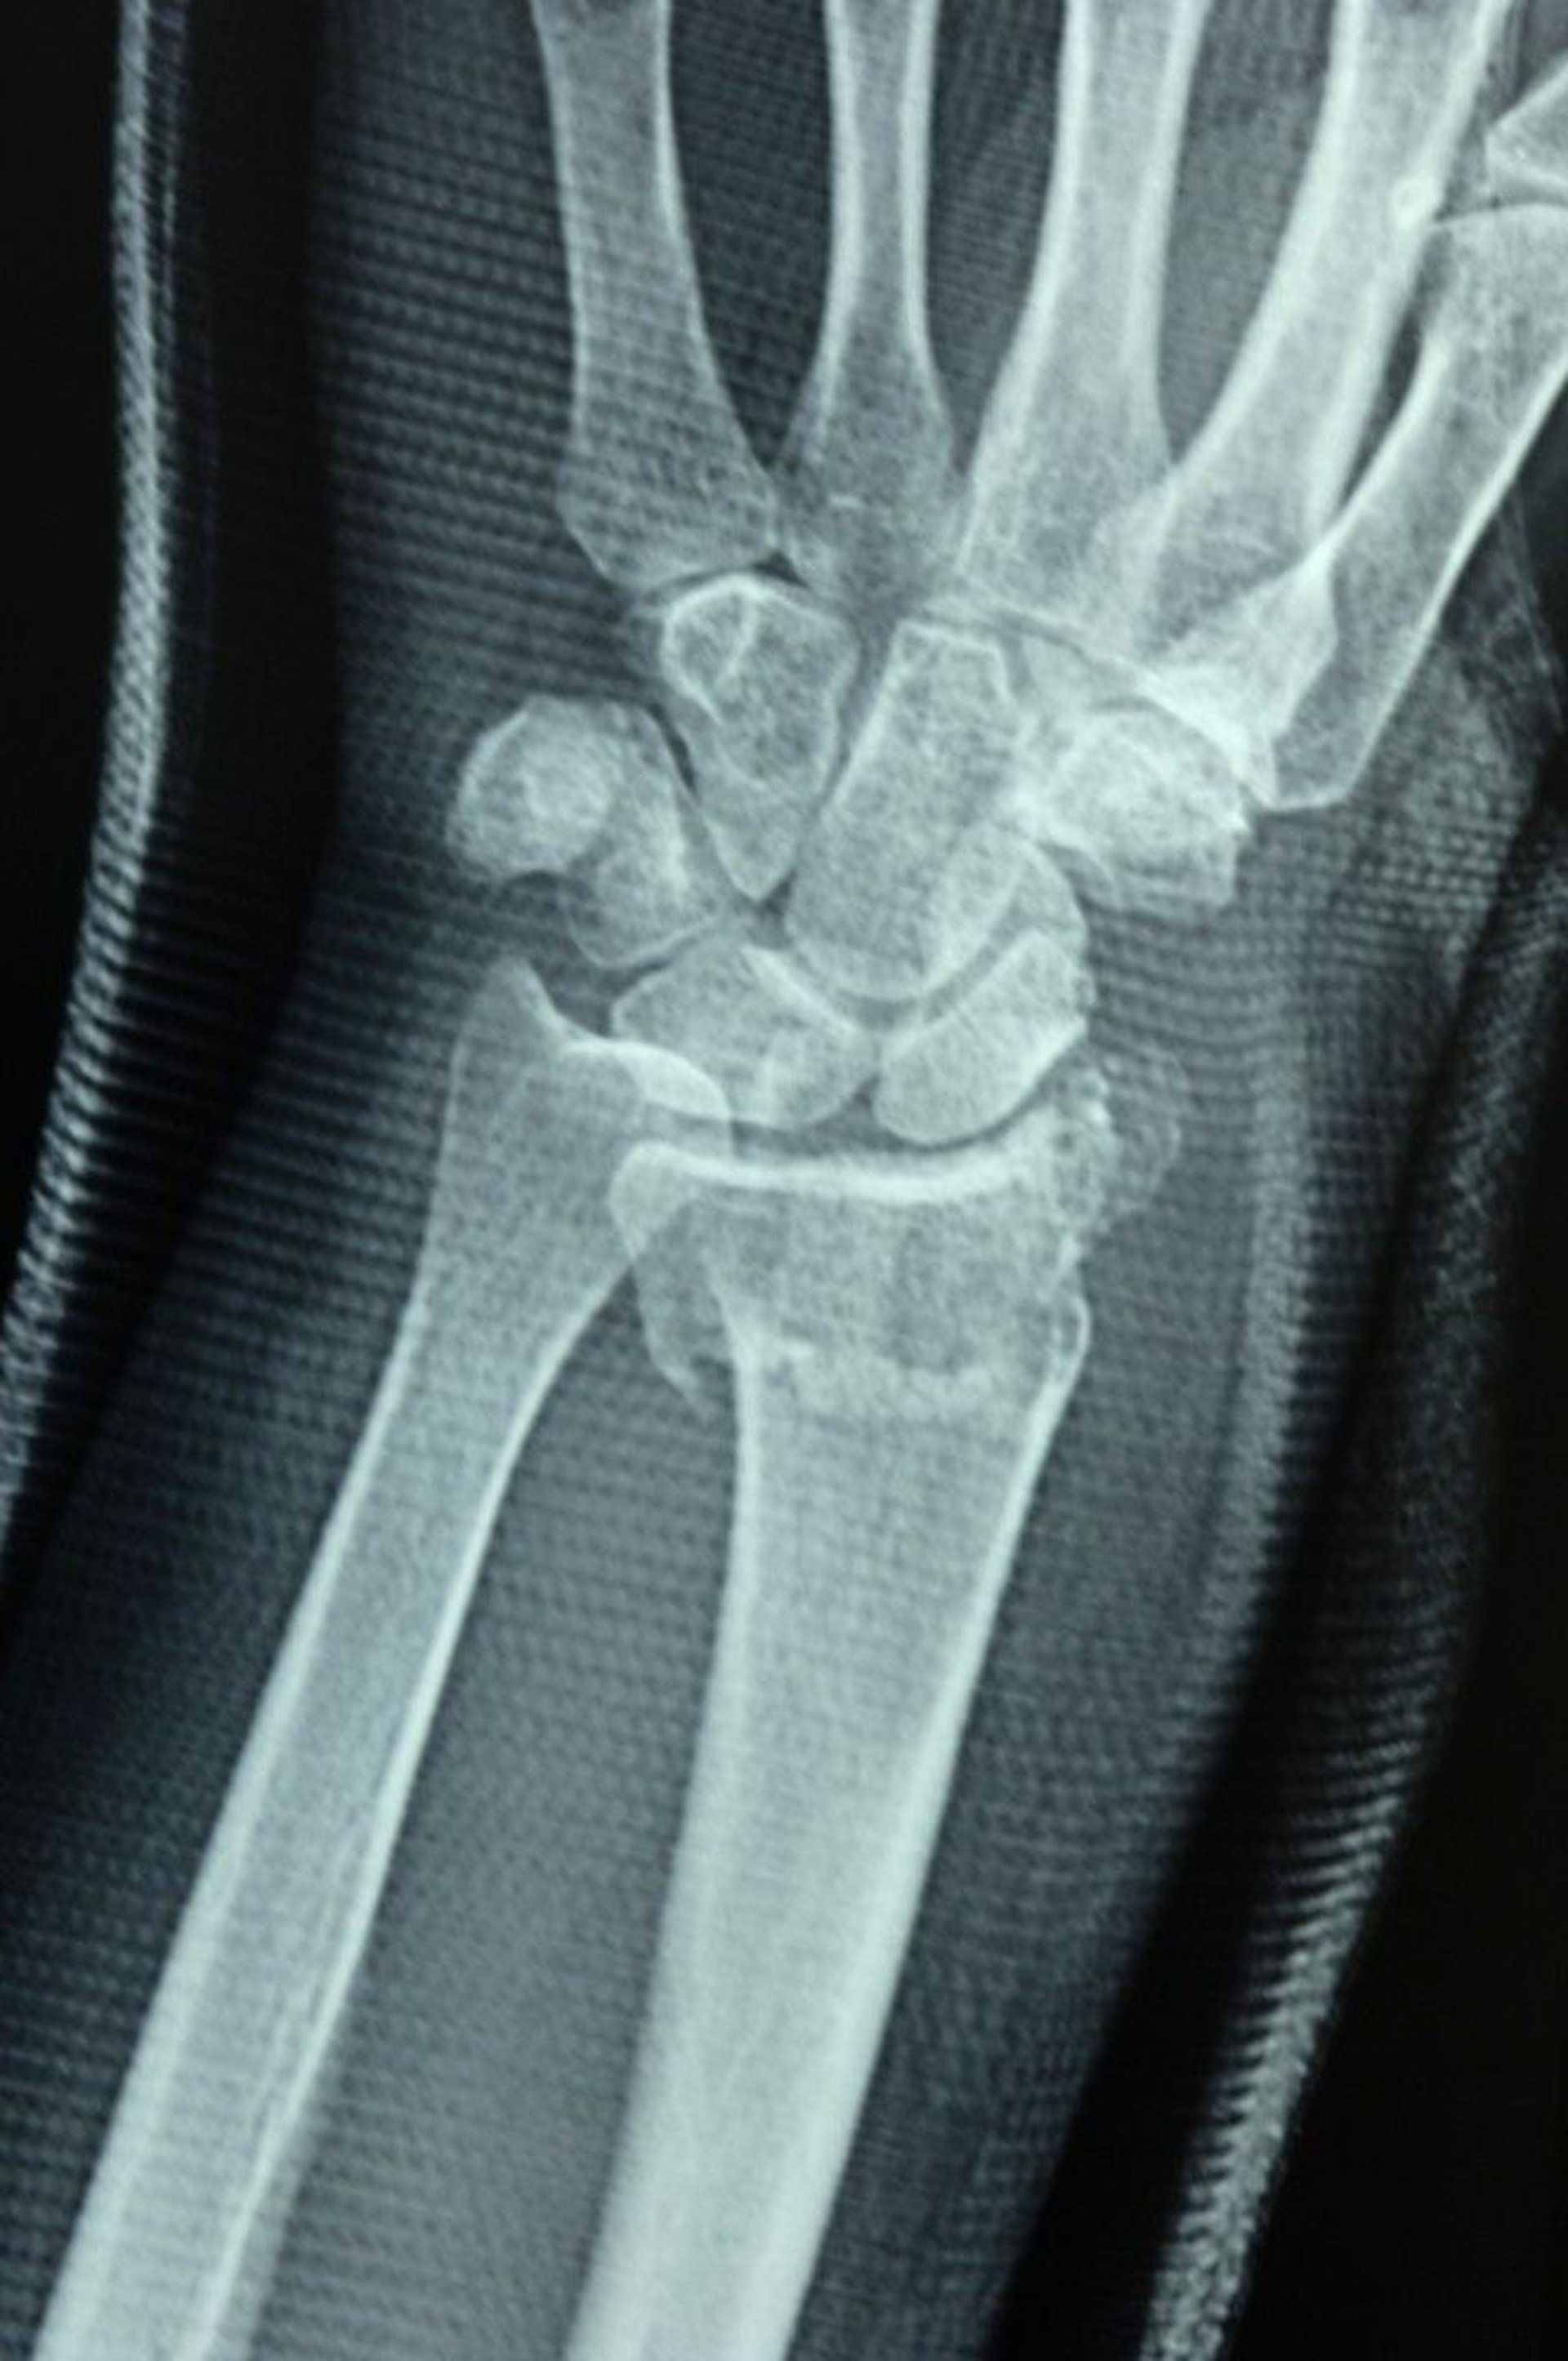

Distal Radius Fracture

The radioulnar joint is disrupted, as shown by the failure of the joint surfaces of the distal radius and distal ulna to align, causing a step-off.